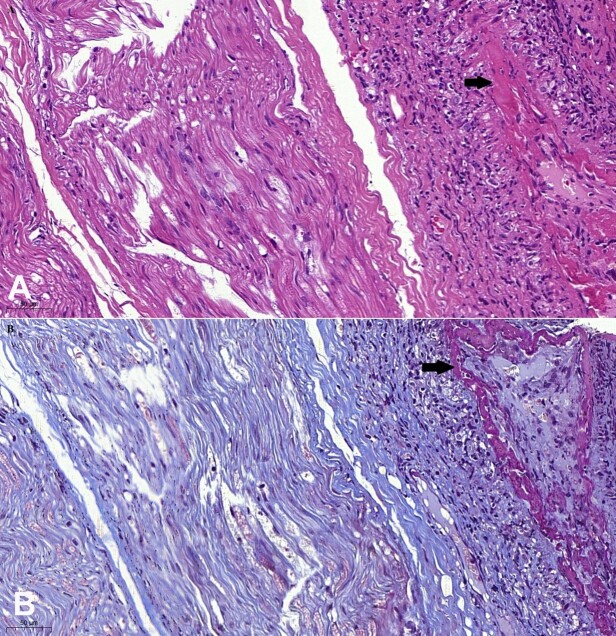

艾滋病病毒感染是一种变色龙,可以模仿多种疾病。在此,我们报告了一名原本健康的 39 岁女性,在 2 个月内出现关节炎、体重减轻和弥漫性多发性单神经病变。广泛的实验室检查显示,她的艾滋病病毒血清学检测呈阳性,CD4 细胞计数为 100,神经活检结果显示坏死性血管炎与 CMV 合并感染无关,因此可以诊断为艾滋病病毒感染者的结节性多动脉炎样血管炎。除感染外,与艾滋病病毒相关的自身免疫可影响任何器官,从而使艾滋病病毒感染的临床表现更加复杂。

HIV infection is a chameleon, mimicking several diseases. Herein, we report a previously healthy 39-year-old woman who, over 2 months, developed arthritis, weight loss, and confluent multiple mononeuropathy. Extensive laboratory investigation showed positive serology for HIV, with a CD4 count of 100 cells, and necrotizing vasculitis on a nerve biopsy not associated with CMV co-infection, allowing the diagnosis of polyarteritis nodosa-like vasculitis in an HIV-infected patient. Apart from the infection, HIV-related autoimmunity can affect any organ and contribute to the complexity of the clinical presentation of HIV infection.